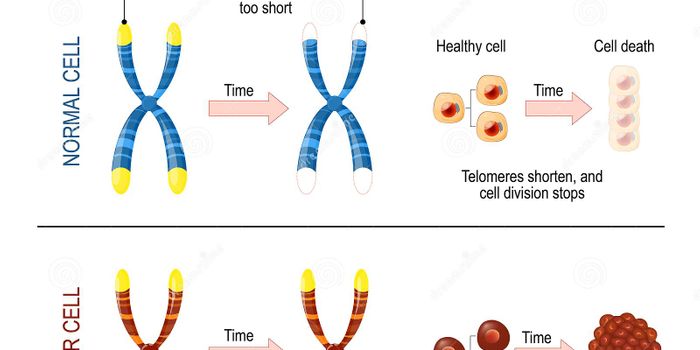

FEB 21, 2023Cell & Molecular BiologyThe Griffith Lab at UNC discovered telomeric protein & potential biomarker VR (green), shown in the nuclei (blue) of hum ...

DEC 16, 2015Clinical & Molecular DXOur society is fascinated by youth and aging. But while some people are on a quest for the “magic” youth cre ...